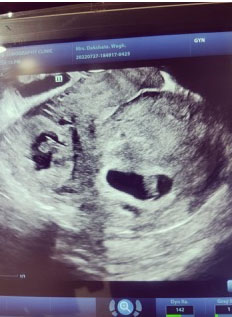

A 36-year-old, gravida 0, presented for schedule abdominal myomectomy for pelvic pain and abnormal uterine bleeding. The patient had no past medical history and no prior abdominal/thoracic surgical history. Transvaginal ultrasound demonstrated an enlarged globular heterogenous uterus with multilobulated contour measuring 13×5.5×5 cm. Hypoechoic solid myometrial masses were present—including an 8.8 cm fundal subserosal, 1.9 cm mid anterior subserosal, 2.7 cm left intramural, and 3.5 cm posterior subserosal fibroid. The patient had an uncomplicated procedure, blood loss of 250 cc with surgery completed in 110 minutes. Myomectomy included removal of a 9 cm fundal subserosal fibroid, 2 cm subserosal fibroid adjoined to the 9 cm fibroid, 3.5 cm posterior subserosal fibroid.